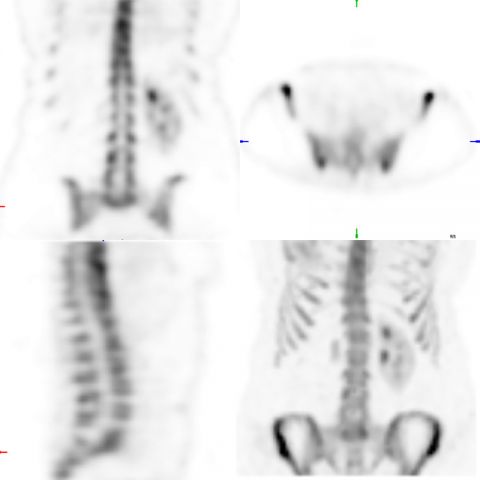

IMAGES